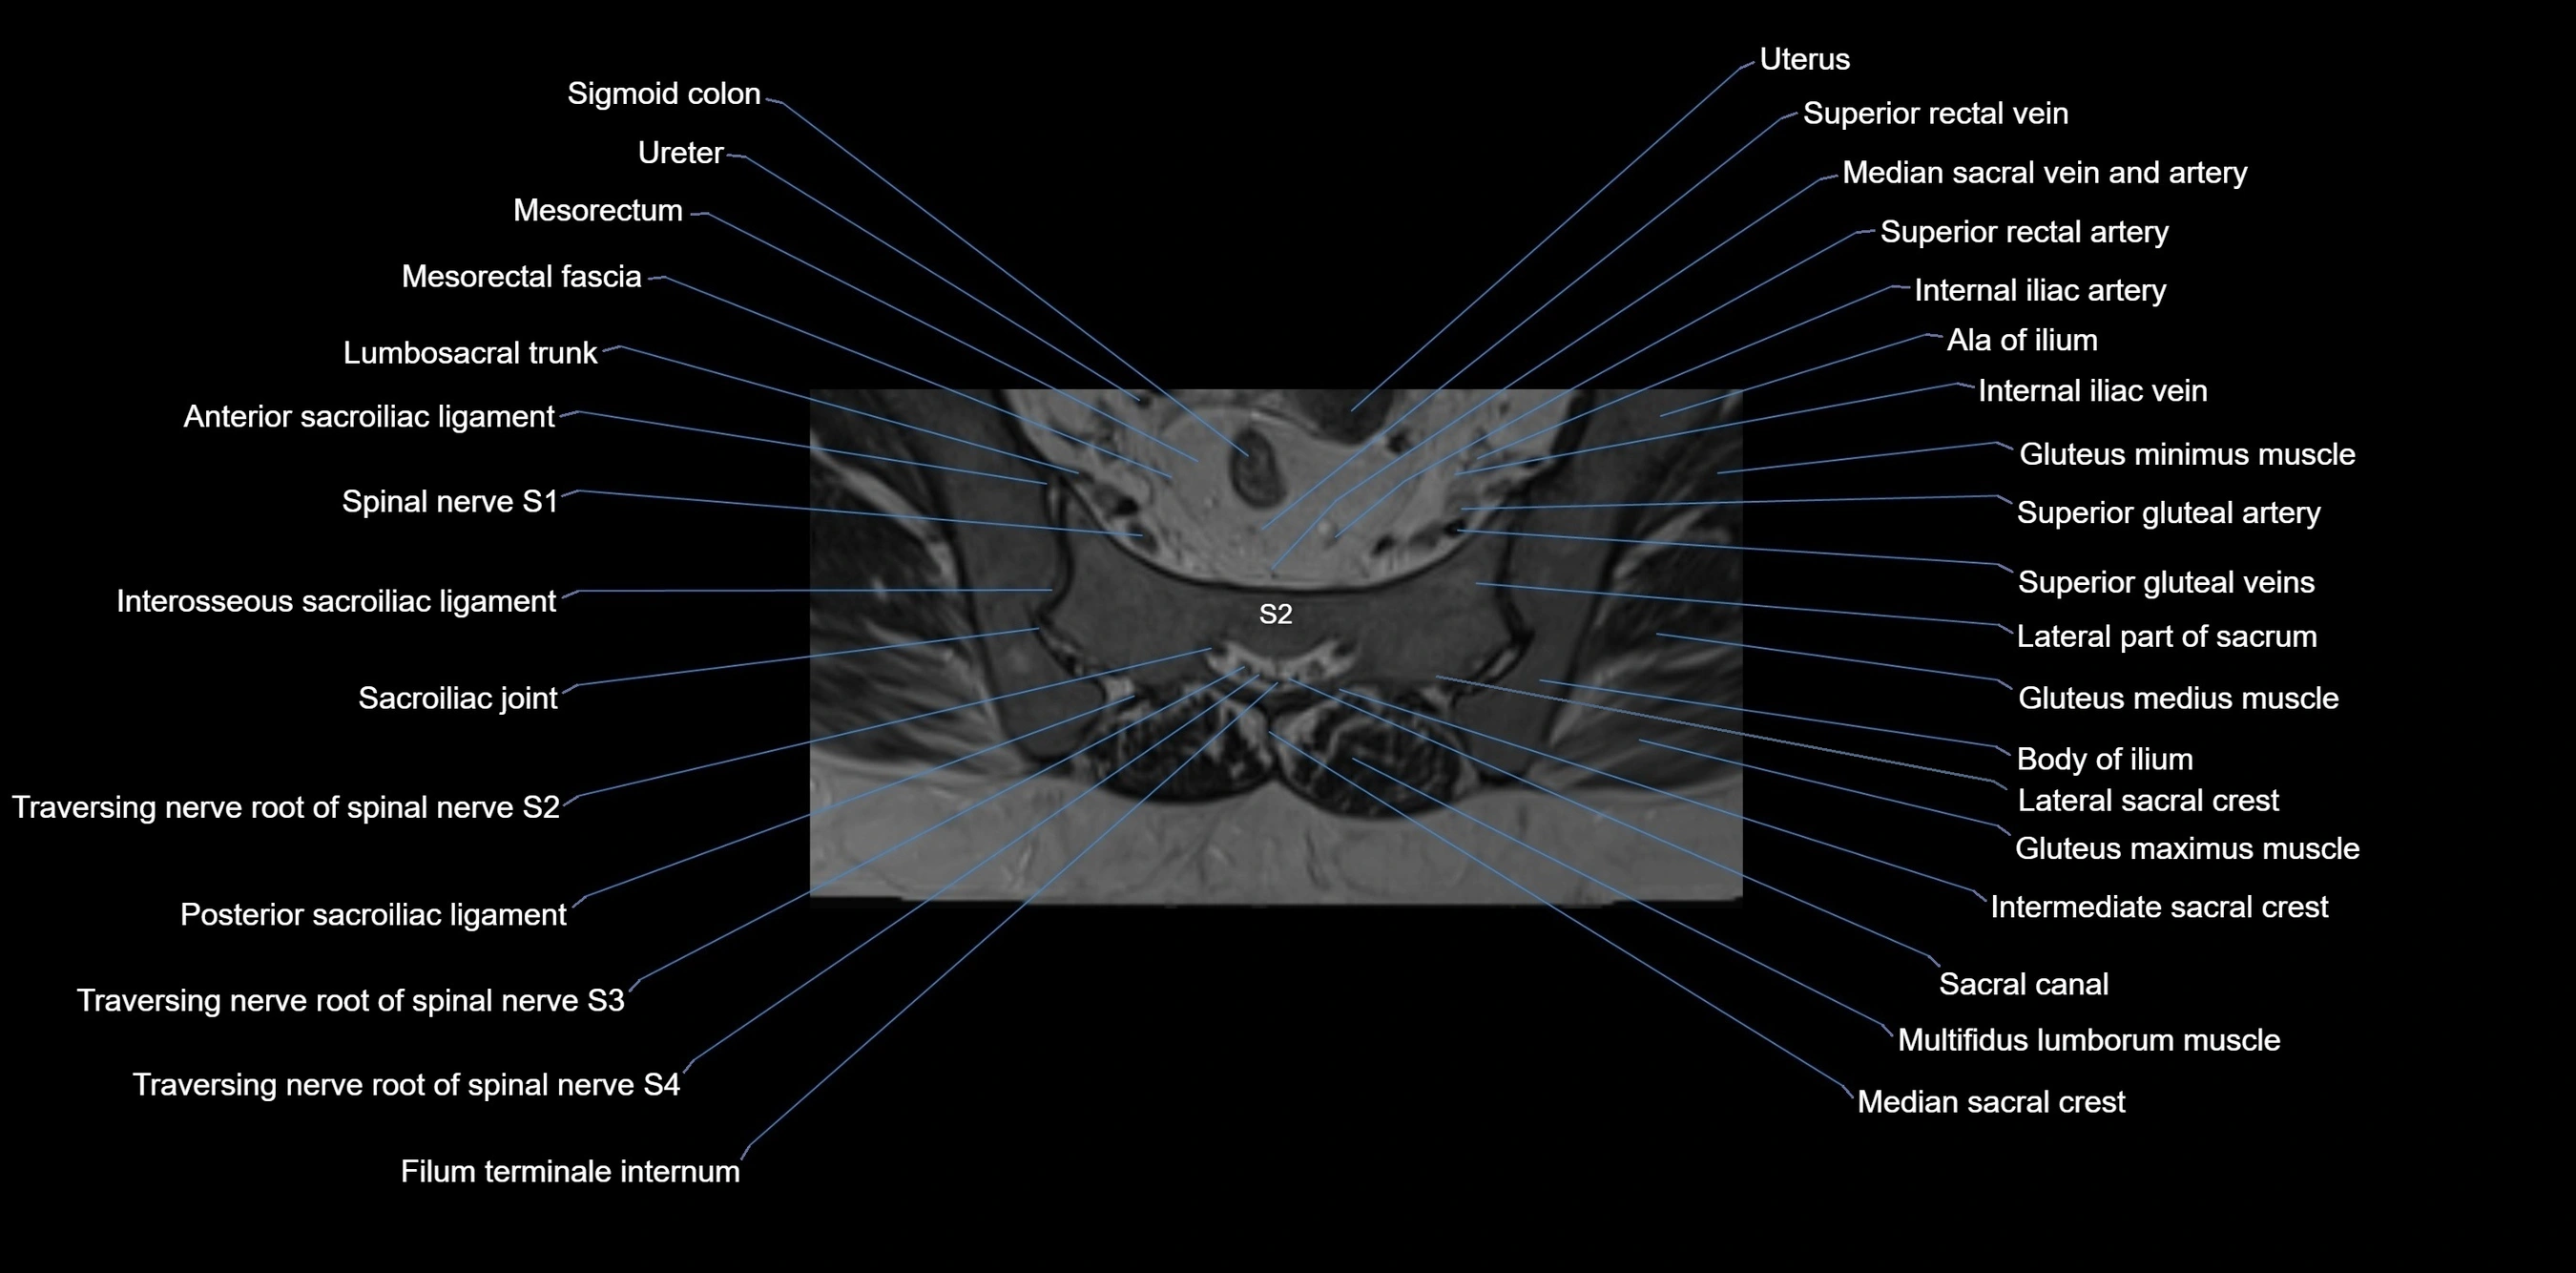

MRI image

image